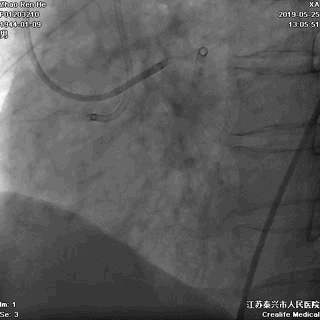

1、逆向导丝抵达闭塞出口,Fielder系列引导,迅速交换CP或Gaia3导丝逆向进攻;

2、灵活使用Knucle技术;

3、前向CP或Gaia3导丝正向准备;

4、正逆向导丝交汇/无限接近;

5、Re-Cart,Kissing Wire,AGT;

6、IVUS评估和优化支架植入。

逆向途径开通RCA